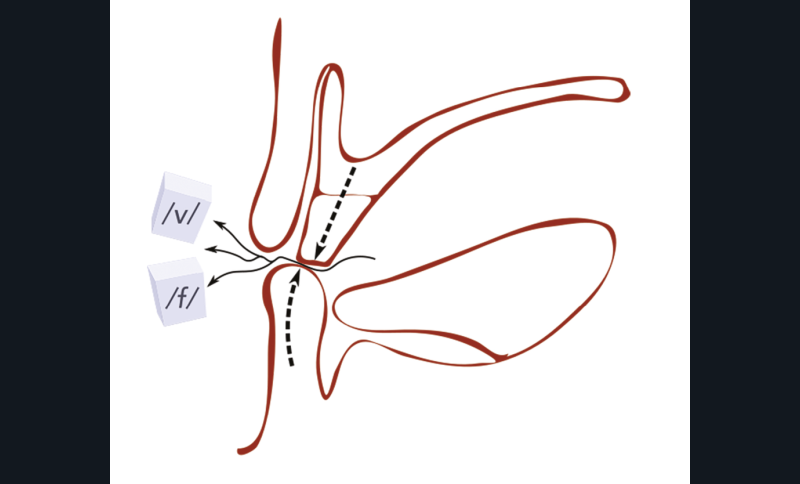

Au niveau phonétique, on teste les phonèmes /f/ et /v/ en faisant prononcer « feu » et « veu » de manière prolongée : le bord vermillon de la lèvre mandibulaire doit se trouver en contact avec les futures incisives maxillaires (fig. 10). Le réglage de la fonction doit conforter le réglage esthétique (fig. 11).